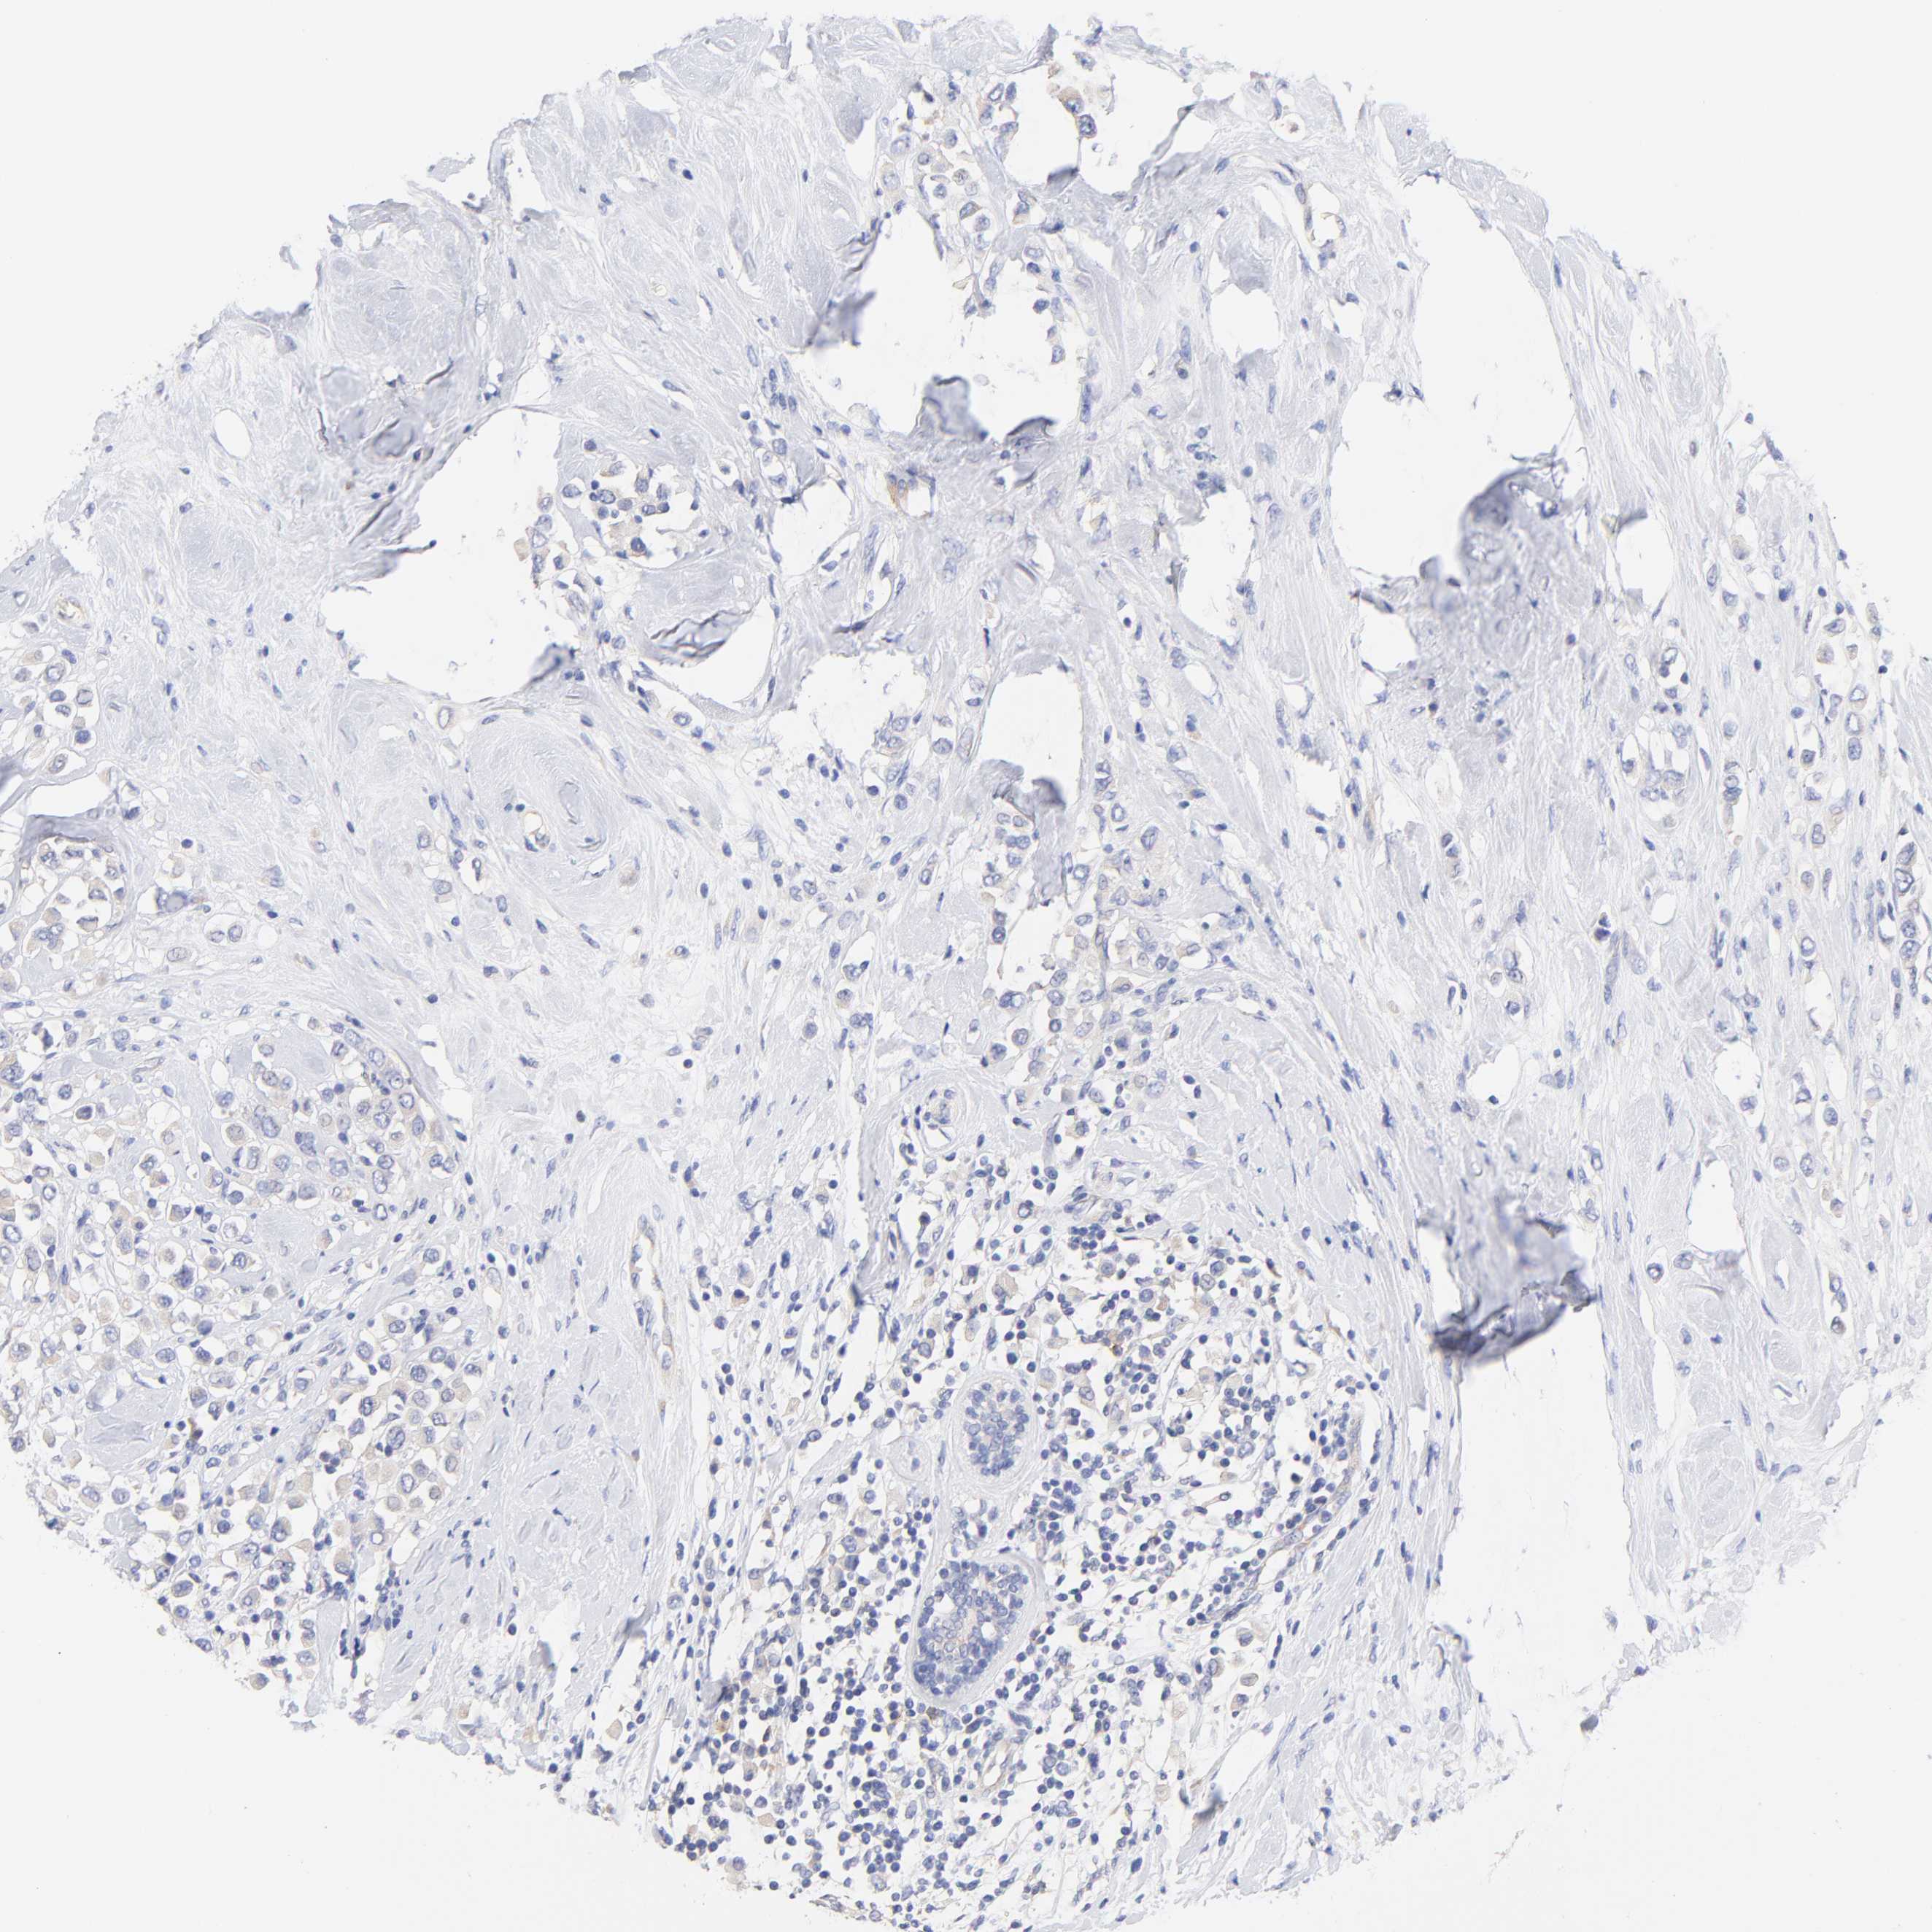

BRCA TCGA BRCA VALIDATION PROTEIN EXPRESSION

ANTIBODIES

AND

VALIDATION